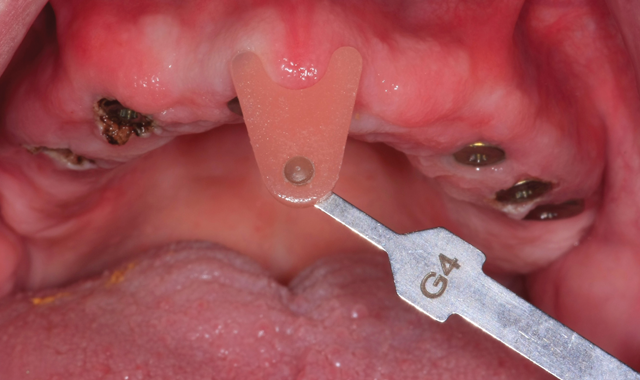

Fig. 16 Try-in the mouth

Final, upside down view of the six implant units (Fig. 16) follow.